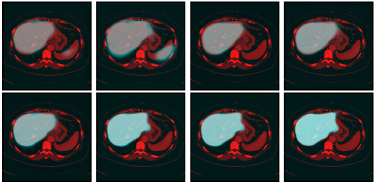

Refer to caption

Figure 3: Iterative results of the liver likelihood map generated by 3D CNNs for one CT volume of database 3Dircabd. From top left to bottom right, the 3rd, 8th, 13th, 20th, 27th, 34th, 42th, and 53th iterative liver likelihood maps are shown. The brighter the region is, the greater the probability of the liver region is

Location of the initial liver region

Before using the network for locating the liver, it should be trained using the cases in the training set. The CNNs is trained for 53 iterations to generate the liver likelihood map. We observe that after the 13th iteration, the heart and spleen, similar to the liver in terms of intensity or texture, can be differentiated from the liver, as shown in Fig. 3. At around the 40th iteration, the validation result converges. During each iteration, a 249×\times249×\times279 block is randomly chosen as the input from a training data, while a 248×\times248×\times256 labeled block as the output. We train the parameters of the proposed 3D CNNs by gradient-based optimization. The partial derivatives are computed using backpropagation Krizhevsky2012ImageNet . We set the learning rate to 0.1/(248×\times248×\times256) at the beginning, and reduce it from 0.1 to 0.005 after the 20th iteration. For other parameters including weight, momentum and decay, we adopt the same as Krizhevsky’s Krizhevsky2012ImageNet . Training the network takes approximately 20 hours using 4 pieces of GTX980 GPUs.

After the training, the probability map of liver can be iteratively learned by the trained 3D CNNs. Fig. 3 illustrates the iterative probability map for a test volume. Then, by thresholding, the initial liver shape L0subscript𝐿0L_{0} is easily located, as shown in red in Fig. 4.